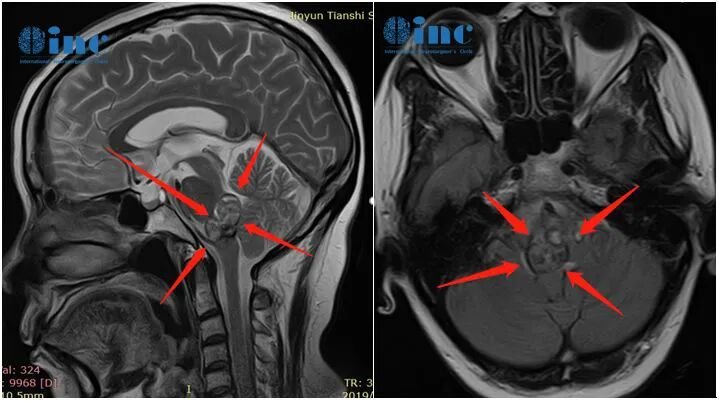

脑桥中部的横断面,并标示了下方的脑桥海绵状血管畸形(PCM)。该血管性病变未紧贴脑桥表面,但单侧性地推移了周围的内在结构,包括外展神经与面神经的神经核团及纤维束。根据解剖学研究,面神经核平均距第四脑室底约5.1毫米,而外展神经核距菱形窝表面的平均距离仅为0.2毫米。绿色箭头指示了抵达此左侧病变的两种可能手术入路:后内侧入路或后外侧入路。p-laterally=后外侧;p-medially=后内侧。